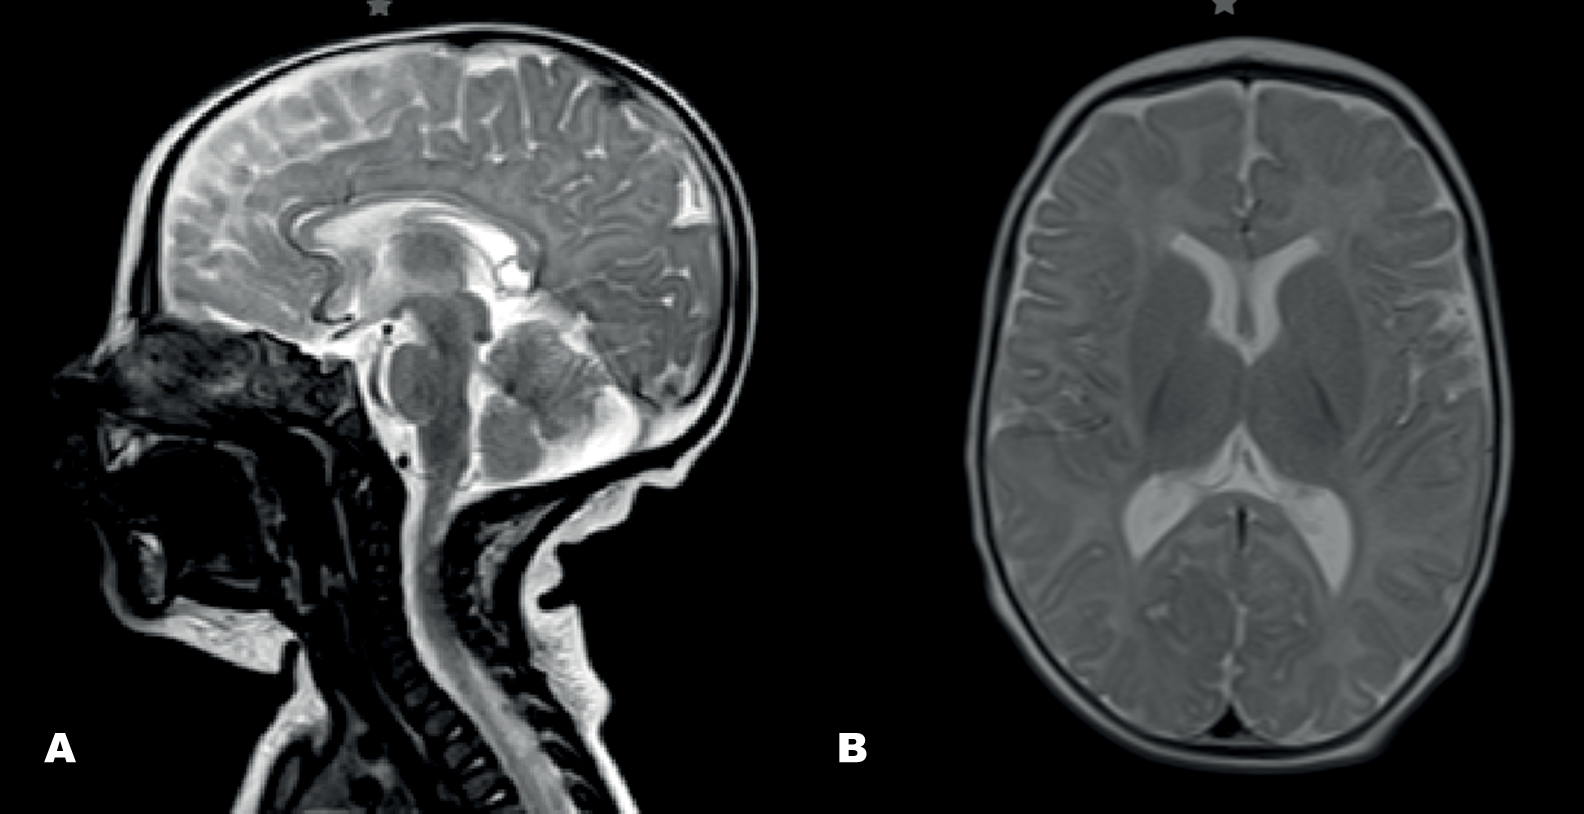

La resonancia magnética cerebral mostró hipoplasia del cuerpo calloso, mega cisterna magna y una variante del síndrome de Dandy-Walker (Figuras 2A y 2B). Los estudios neurofisiológicos (electroencefalograma, electromiograma y pruebas auditivas) no arrojaron hallazgos significativos. Ante la persistencia de hallazgos clínicos, se solicitó un estudio genético de miopatías mitocondriales (ADN mitocondrial más panel de genes nucleares mitocondriales), el cual resultó negativo. Posteriormente, se amplió la evaluación genética con un panel de atrofias ópticas sindrómicas, donde se identificó una mutación en heterocigosis en el exón 18 del gen ATP1A3 (NM_152296) c.2452G>A; p.Glu818Lys, descrita como patogénica en bases de datos como CLINVAR y responsable del síndrome CAPOS/CAOS, con herencia autosómica dominante2. El estudio de segregación familiar confirmó que se trataba de una mutación de novo, correspondiendo así a un caso esporádico.

Figura 2. Imágenes por resonancia magnética cerebral en cortes sagital (Figura A) y axial (Figura B), secuencia T2

Fuente: expediente clínico del paciente.

Se observa hipoplasia del cuerpo calloso, presencia de una mega cisterna magna y hallazgos compatibles con una variante del síndrome de Dandy-Walker, caracterizada por vermis cerebeloso hipoplásico y agrandamiento de la fosa posterior.